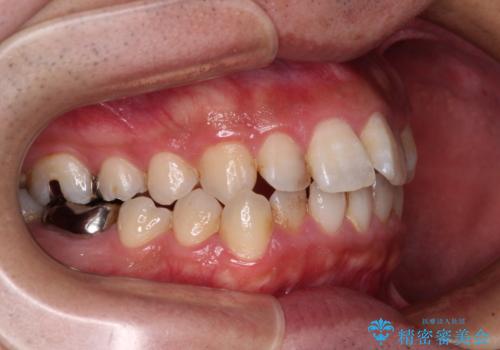

前歯のデコボコと突出感をマウスピース矯正できれいに

- 上下前歯のデコボコと突出感を気にして来院された患者様です。

目立たない装置を希望されたため、インビザラインによるマウスピース矯正を行うこととしました。

矯正治療後に銀歯をセラミックに替えたいとの要望があり、概ね歯列が整ったところで銀歯をセラミックに替え、仕上げにインビザライン1セットを使用して最終的に歯列を整えました。